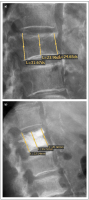

Möglichkeiten der direkten Zementinjektionstechnik bei Wirbelkörperfrakturen - Drei Fallbeschreibungen der Radiofrequenz-Kyphoplastie (RFK) mit ultrahochvikösem Knochenzement

Journal für Mineralstoffwechsel & Muskuloskelettale Erkrankungen 2012; 19 (3): 124-130 Volltext (PDF) Summary Praxisrelevanz Abbildungen